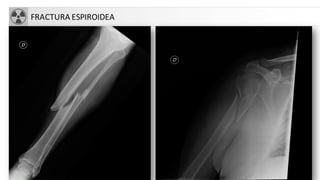

FRACTURA ESPIROIDEA

C. Espiroidea